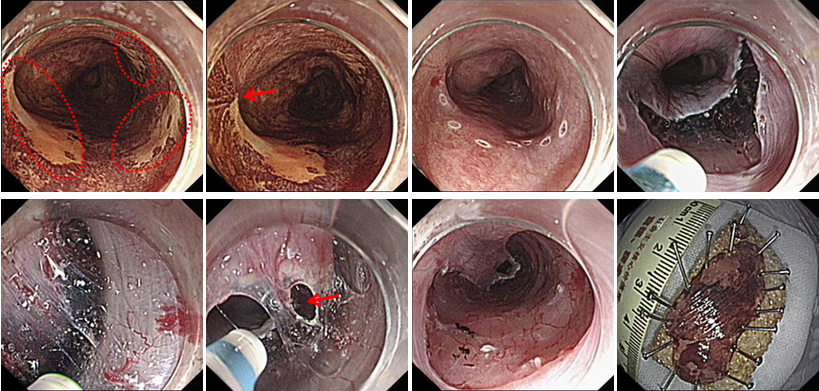

⑤ESD

随着内镜微创技术的发展,越来越多的早期消化道癌、癌前病变及胃肠黏膜下疾病可完全在内镜下予以切除,免除了更大的手术创伤,这就是内镜黏膜下剥离术ESD(endoscopic submucosal dissecfion)

该治疗具有不改变消化道解剖结构、不开刀、体表无创口、创伤、出血少、恢复快等优势,是近年来国际、国内最新兴起的内窥镜下微创治疗手段之一,适用于食管、胃、十二指肠等上消化道及结、直肠的黏膜下良性肿瘤、黏膜的早期癌变以及具有癌变倾向病变的切除治疗。因其特殊的微创优势,得到广大医生及患者的推崇,是消化道黏膜及黏膜下病变治疗的新兴发展趋势。我中心已经开展该项技术,技术成熟,并还开展了经口内镜下肌切开术POEM、内镜经粘膜下隧道肿瘤切除术STER、粘膜下隧道内镜剥离术ESTD,术后病人随访,恢复良好。

Ⅲ、POEM治疗贲门失弛缓症

Ⅳ、ESTD治疗多灶性复发型食管早癌

Ⅴ、ESTD治疗超低位大面积直肠早癌

Ⅵ、STER治疗食管固有肌层肿瘤